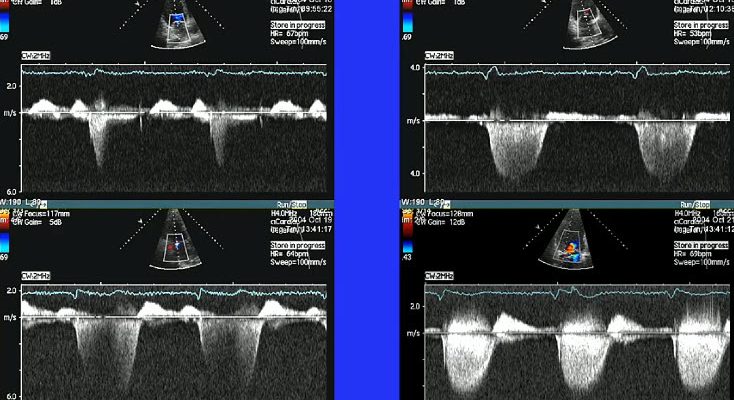

ИИ на страже сердца: наш опыт разработки системы анализа ЭхоКГ для диагностики митральной регургитации В современном мире, где технологии проникают во